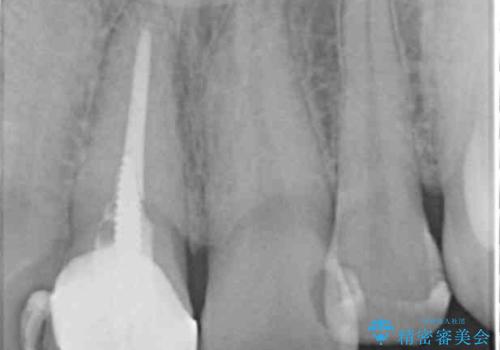

- 奥に引っ込んでいる前歯を矯正治療で並べたい!色の気になる前歯のクラウンをやり替えたい!と希望され来院されました。

奥に位置している前歯を部分ワイヤー矯正ののちマウスピース矯正インビザラインで並べ、矯正治療後に審美的なジルコニアクラウンを作製していきます。